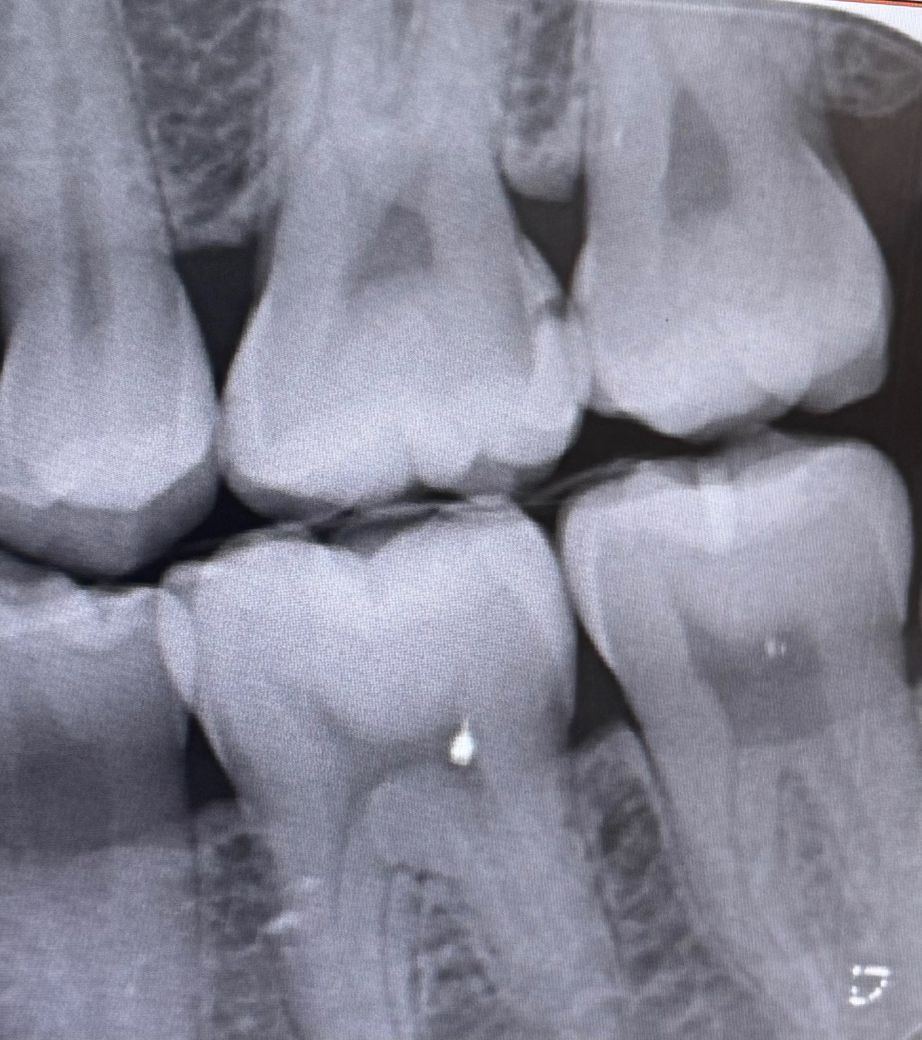

인접면 충치치료 후 질문합니다 답변 부탁드려요

열흘전에 인접면 충치치료 후 레진으로 씌웠는데 치실하면 시리고 뭐 씹을때마다 시려서 3일전에 레진 갈고 다른 재료로 매꾸고 경과지켜보고 다시 레진으로 채울거라고 하셨는데 지금 매꾼 재료가 살짝 떨어진거같고 엄청 시린데 당장 병원가여하나요? 내일이 진료 예약있는날인데 오늘 당장 가야하나해서요

제 충치가 많이 깊어서 신경치료를 했어야하는 정도인가요? 아님 지켜봐도 되는 정도일까요 일단 충치는 제거했는데 계속 이가 시리면 신경치료 해야할수도 있다고 들어서요 정말 하기싫은데 ㅠㅠ

• 1번 째 사진

엑스레이상으론 신경치료까지는 아닐 가능성이 높고요.

임시로 떼워놓은 재료가 떨어졌으니 시린 건 당연합니다.

하루정도 버틸 수 있다면 원래 약속날 가시고, 안되겠으면 바로 가시면 됩니다.